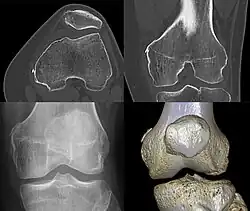

Diagnosis is typically made on radiographs demonstrating the Pellegrini-Stieda syndrome sign accompanied by pain or restriction of range-of-motion of the knee joint.[2] Pellegrini-Stieda syndrome sign is typically described by a longitudinally linear opacity, which is a process that is describes characteristic of calcification in the soft tissue located medial to the medial femoral condyle.[2] This calcification seen on imaging represents the ossification of the medial collateral ligament, which typically does not develop until approximately three weeks after the initial injury.[2]It is important to note to distinguish this radiographic finding from that of a medial femoral condyle avulsion fracture, which is an injury in which a pulling force of a tendon or ligament fractures away a piece of the bone from its attachment site.[2]

Alternative classification syndrome for Pellegrini-Stieda lesions of Type 1 through Type 4 based on their location:[2]

- Type 1- is referred to as a beak-like appearance and describes the ossification arising from the femur and extending inferiorly in the medial collateral ligament.

- Type 2-is defines a tear-drop pattern, localized within the medial collateral ligament without any attachment to the femur.

- Type 3-presents as an elongated ossification superior to the femur lying in the distal adductor magnus tendon.

- Type 4-is also characterized as a beak-like appearance arising from the femur. However, there are some cases where this ossification extends into both the medial collateral ligament and adductor magnus tendon. In then, the original attribution of the syndrome to the medial collateral ligament may now be outdated as many publications have suggested concomitant and even sometimes preferential involvement of the adductor magnus tendon, medial head of the gastrocnemius, or medial patellofemoral ligament.[2]